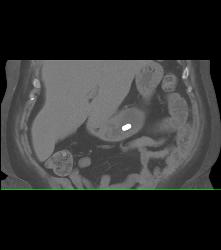

Gastric Outlet Onstruction to Tumor